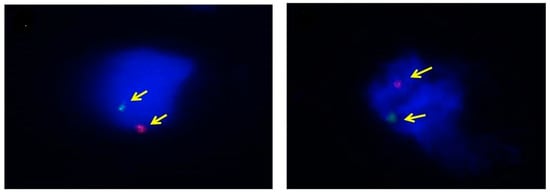

2.5. Fluorescence in Situ Hybridization (FISH)

| Sample ID | GA (Days) | Karyotype (Genetic Test) | Karyotype (FISH) | Fetal Sex (after Delivery) | Number. of Cells (XY/Total) | Y Detection | |||

|---|---|---|---|---|---|---|---|---|---|

| Rate (%) | Mean ± SD | p-Value | |||||||

| Pre- Fixation (ThinPrep) | 1 | 119 | XX | XX | Female | 11.1 ± 2.1 | 0.001 | ||

| 2 | 87 | XY | XY | Male | 3/35 | 8.6 | |||

| 4 | 50 | XY | XY | Male | 7/52 | 13.5 | |||

| 5 | 58 | XY | XY | Male | 5/47 | 10.6 | |||

| 10 | 72 | XY | XY | Male | 6/51 | 11.8 | |||

| Post- Fixation (Formalin) | 1 | 77 | XY | XY | Male | 15/51 | 29.4 | 23.8 ± 4.8 | |

| 2 | 54 | XY | XY | Male | 12/52 | 17.8 | |||

| 6 | 112 | XY | XY | Male | 13/45 | 28.9 | |||

| 8 | 112 | XY | XY | Male | 12/50 | 24.0 | |||

| 9 | 117 | XY | XY | Male | 8/30 | 23.3 | |||

| 10 | 96 | XY | XY | Male | 12/62 | 19.4 | |||